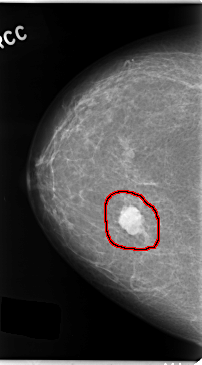

C_0131_1.RIGHT_CC

RIGHT_CC LINES 4736 PIXELS_PER_LINE 2616 BITS_PER_PIXEL 12 RESOLUTION 50 OVERLAY

FILE: C_0131_1.RIGHT_CC.OVERLAY

TOTAL_ABNORMALITIES 1

ABNORMALITY 1

LESION_TYPE MASS SHAPE LOBULATED MARGINS CIRCUMSCRIBED

ASSESSMENT 5

SUBTLETY 5

PATHOLOGY MALIGNANT

TOTAL_OUTLINES 1

BOUNDARY